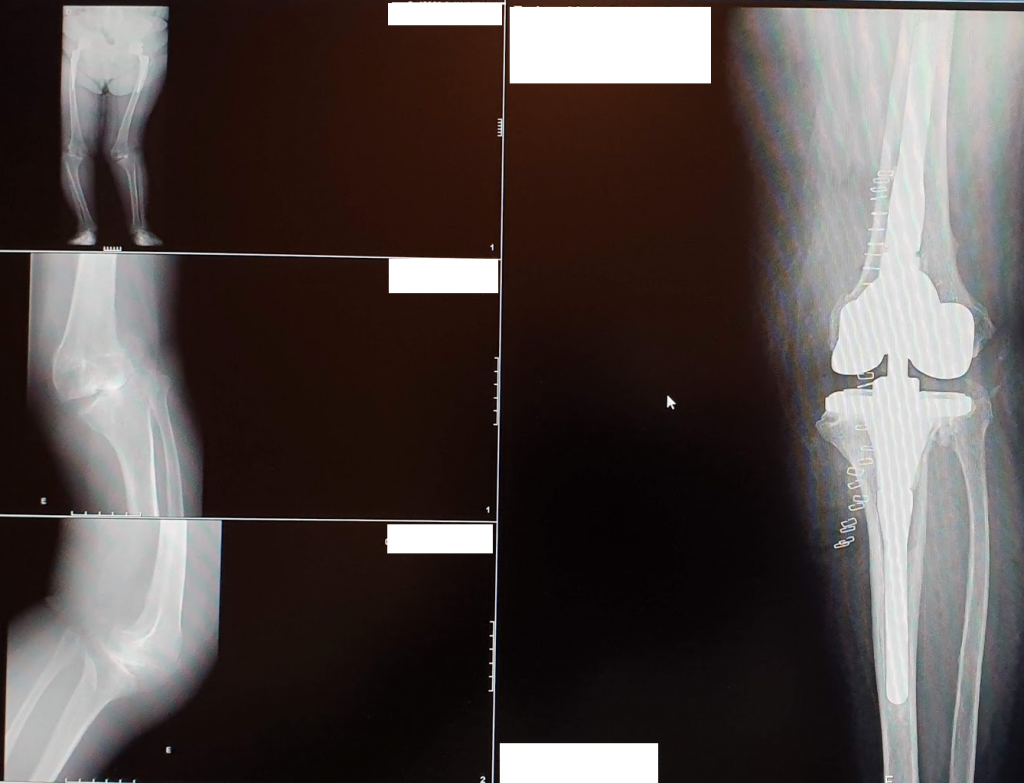

- Radiografias – de face e perfil em carga , extralongo em carga que permitem realizar um diagnostico e avaliar de forma efetiva o grau de comprometimento articular

Porque cada doente é diferente, também a prótese do joelho deverá ser adaptada ao doente. Para isso é fundamental um estudo adequado pré-operatório centrado nas particularidades do doente e da sua condição clínica, e o estabelecimento dos objetivos a atingir.

A chamada prótese unicompartimental permite substituir apenas a parte do joelho mais desgastada e manter o restante, diminuindo os riscos a longo prazo e melhorando a proprioceção, obtendo-se por isso um joelho muito mais natural.

SABIA QUE JÁ EXISTEM PRÓTESES COM MOLDES PERSONALIZADOS FABRICADOS À MEDIDA DE CADA DOENTE?

Neste momento já estão disponíveis abordagens personalizadas que usam imagens pré‐operatórias para criar moldes de corte específicos à anatomia de cada doente, permitindo otimizar o resultado final e a satisfação do doente com a sua prótese.